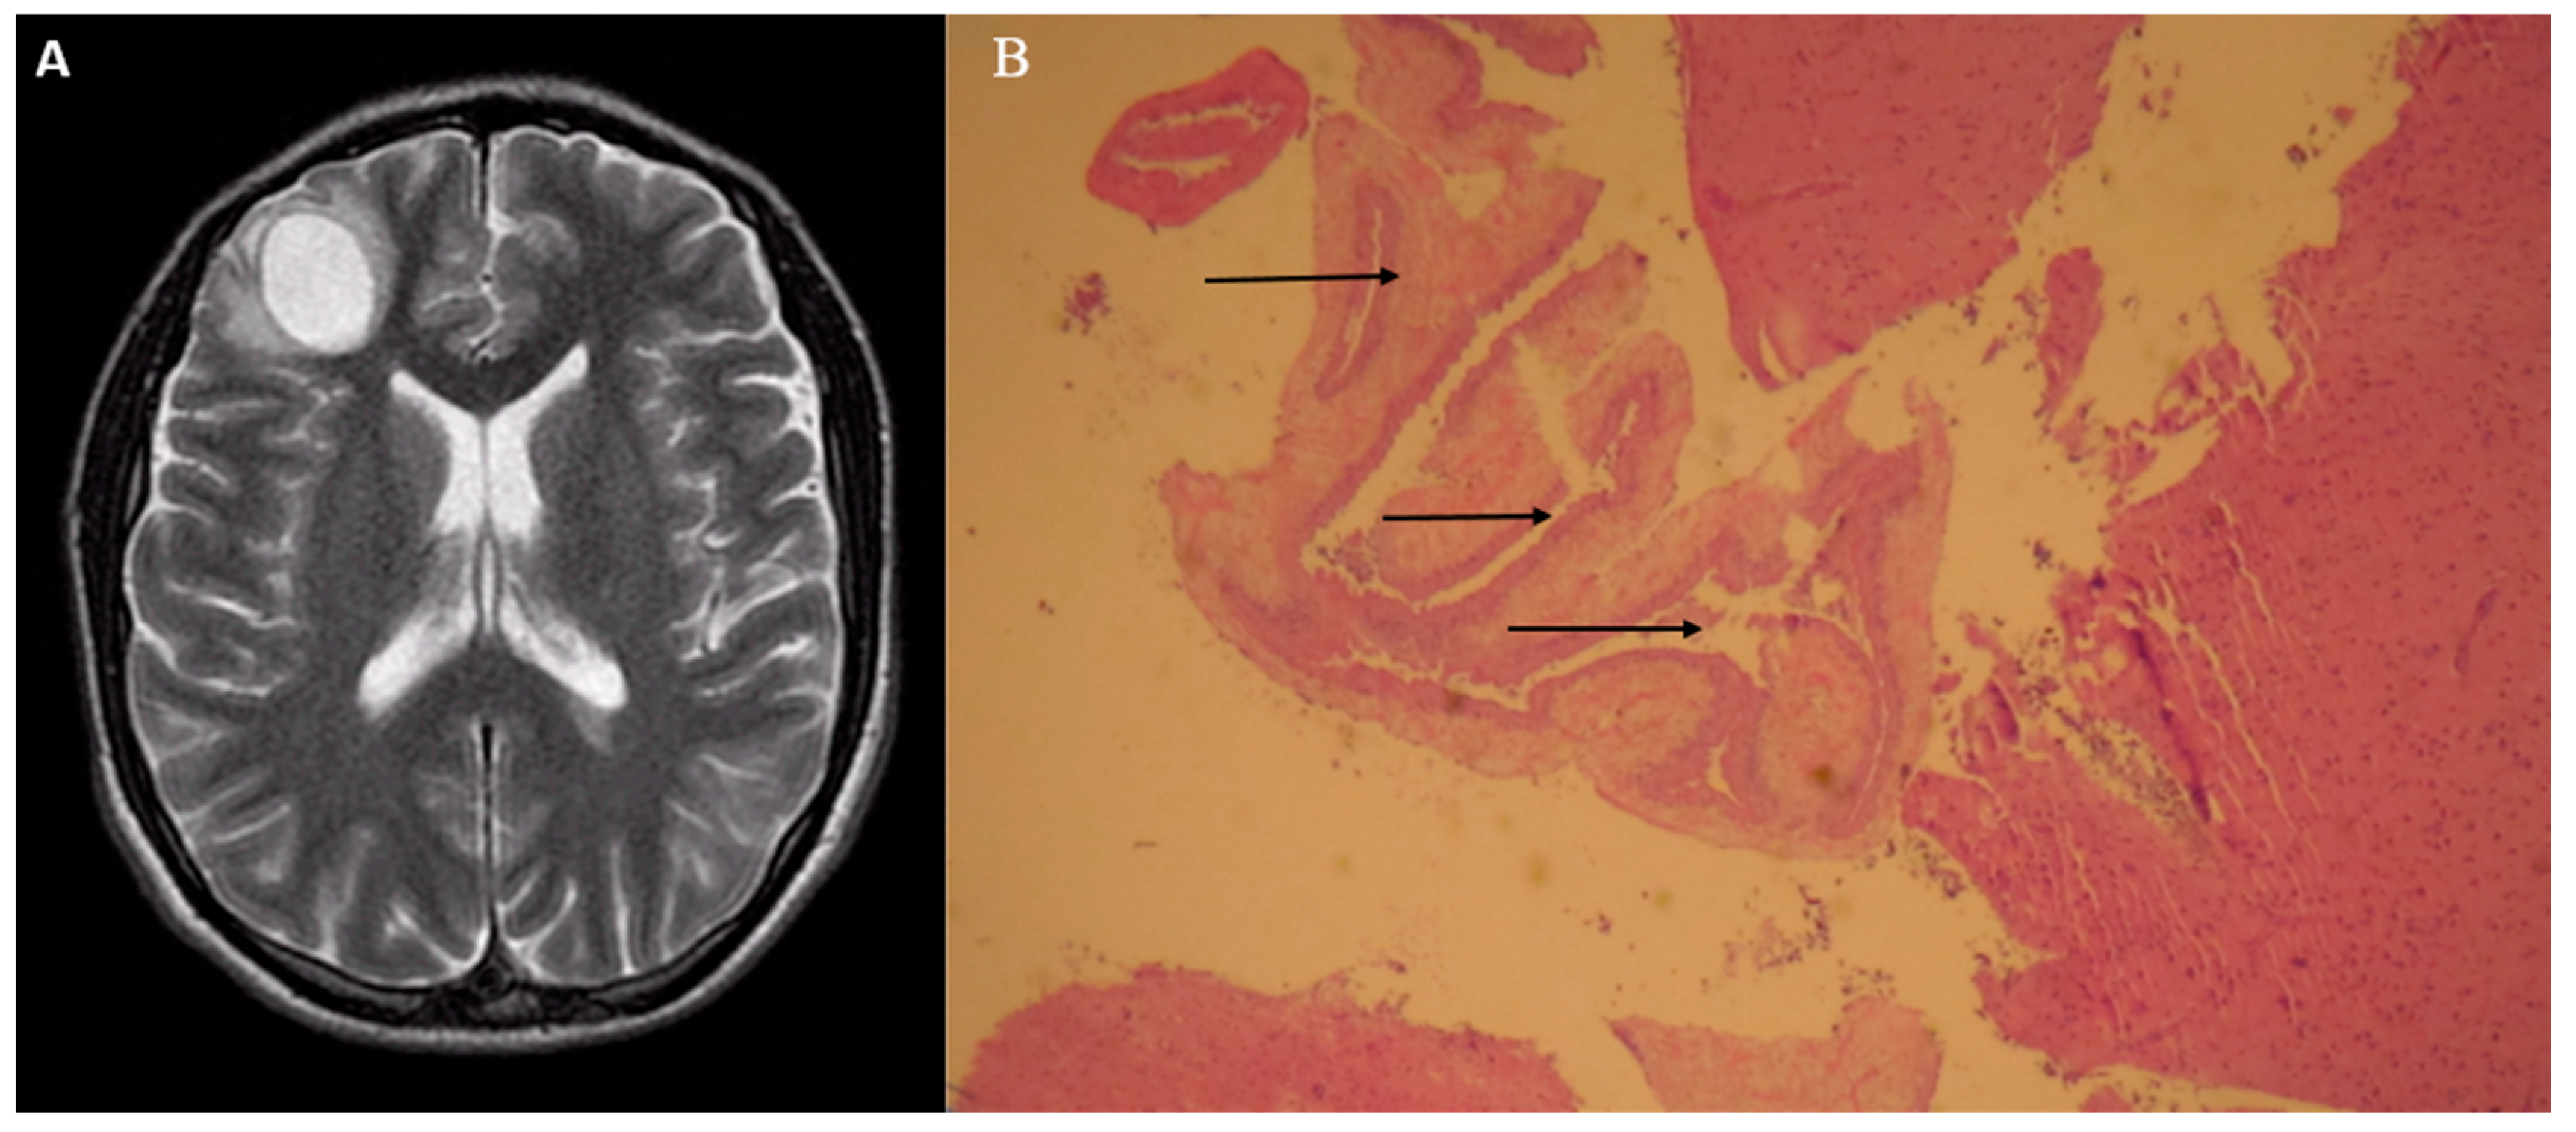

A 24-year old Hispanic man was found unresponsive at home after having multiple episodes of complex partial seizures. He was originally from Mexico and traveled there three weeks prior to hospital admission. His neurological exam did not reveal any focal deficits. He was intubated for airway protection and treated with fosphenytoin. A magnetic resonance imaging (MRI) with gadolinium contrast was ordered. T2-weighted imaging showed a cystic lesion of 2.2 × 2.5 cm in diameter with surrounding edema in right frontal lobe (A). Western blot serology for Echinococcus and cysticercosis was negative. Due to the concern for a neoplastic process and negative serology for parasitosis, computed tomography (CT) of chest, abdomen, and pelvis was ordered, which was unremarkable. The patient underwent craniotomy with resection of the mass. On gross inspection, the mass appeared cystic. Histopathology with hematoxylin and eosin (H&E) staining revealed benign brain parenchyma with degenerated fragments of a parasite consistent with Taenia solium (B). The patient was treated with albendazole for 14 days. No further seizures were noted at 6-month follow-up. Neurocysticercosis is a parasitosis caused by the larval stage of the pork tapeworm Taenia solium. It can be associated with various neuroimaging findings including solitary mass, which can be a diagnostic dilemma. Neurocysticercosis typically involve the cerebral hemispheres, with lesions found at the gray-white matter junction. In individuals with multiple lesions, the basal ganglia, cerebellum and brainstem may be affected. The appearance of these brain lesions on neuroimaging depends on their stage of involution. Four stages can be recognized on CT or MRI: vesicular, colloidal, granular nodular, and calcified lesions [1]. Live vesicular cysts are small and rounded lesions with little or no pericystic edema, not enhanced with contrast. The cyst fluid usually demonstrates the same signal intensity of cerebrospinal fluid on all MRI sequences. In this stage, the scolex is frequently identified as an internal asymmetric nodule in the cyst. Fluid-attenuated inversion recovery (FLAIR) imaging can improve the visualization of the T2-weighted hyperintense scolex [1]. After the degenerative process becomes established (colloidal stage), the cysts show poorly defined borders with surrounding edema. MRI usually reveals ring contrast enhancement [2]. At this stage, absence of diffusion restriction is evident on diffusion-weighted (DW) imaging, which helps to distinguish these lesions from abscesses. In the granular nodular stage, the lesions are smaller and imaging demonstrate hyperintense rims, representative of gliosis [2]. Calcified nodules are the end stage of cysticercal degeneration and can be seen as hyperdense lesions with no associated edema or enhancement. CT is the most sensitive imaging to identify lesions at this stage [1]. In terms of clinical manifestations, patients may remain asymptomatic, particularly with viable non-degenerating cysts; however, seizures are the most common presentation in cases of degenerating cysts that produce an injurious inflammatory response [3]. In patients with single parenchymal lesions, the diagnosis is challenging, as morphology on neuroimaging can be inconclusive and serology is commonly negative [4]. In endemic regions, neurocysticercosis may be confounded with other infections that affect the brain parenchyma such as tuberculosis, owing to similar radiographic appearance [5]. Albendazole is the treatment of choice, which should be administered with corticosteroids to reduce the inflammation associated with dying organisms [6,7]. Our case highlights the importance of considering neurocysticercosis in the differential diagnosis of solitary brain masses, especially in patients coming from endemic countries. The radiographic features of this condition vary depending on the stage of involution of the cysts. They are best visualized by MRI in early stages, while CT is the preferred imaging at the end stage of cysticercal degeneration.